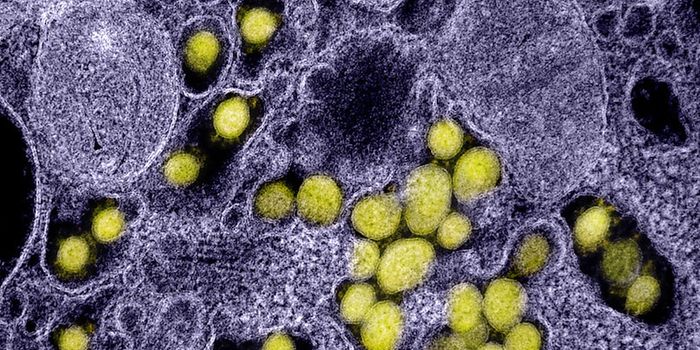

SEP 20, 2021Genetics & GenomicsHuman immunodeficiency virus (HIV) is a retrovirus, which is a type of virus that can write its genetic material into th ...